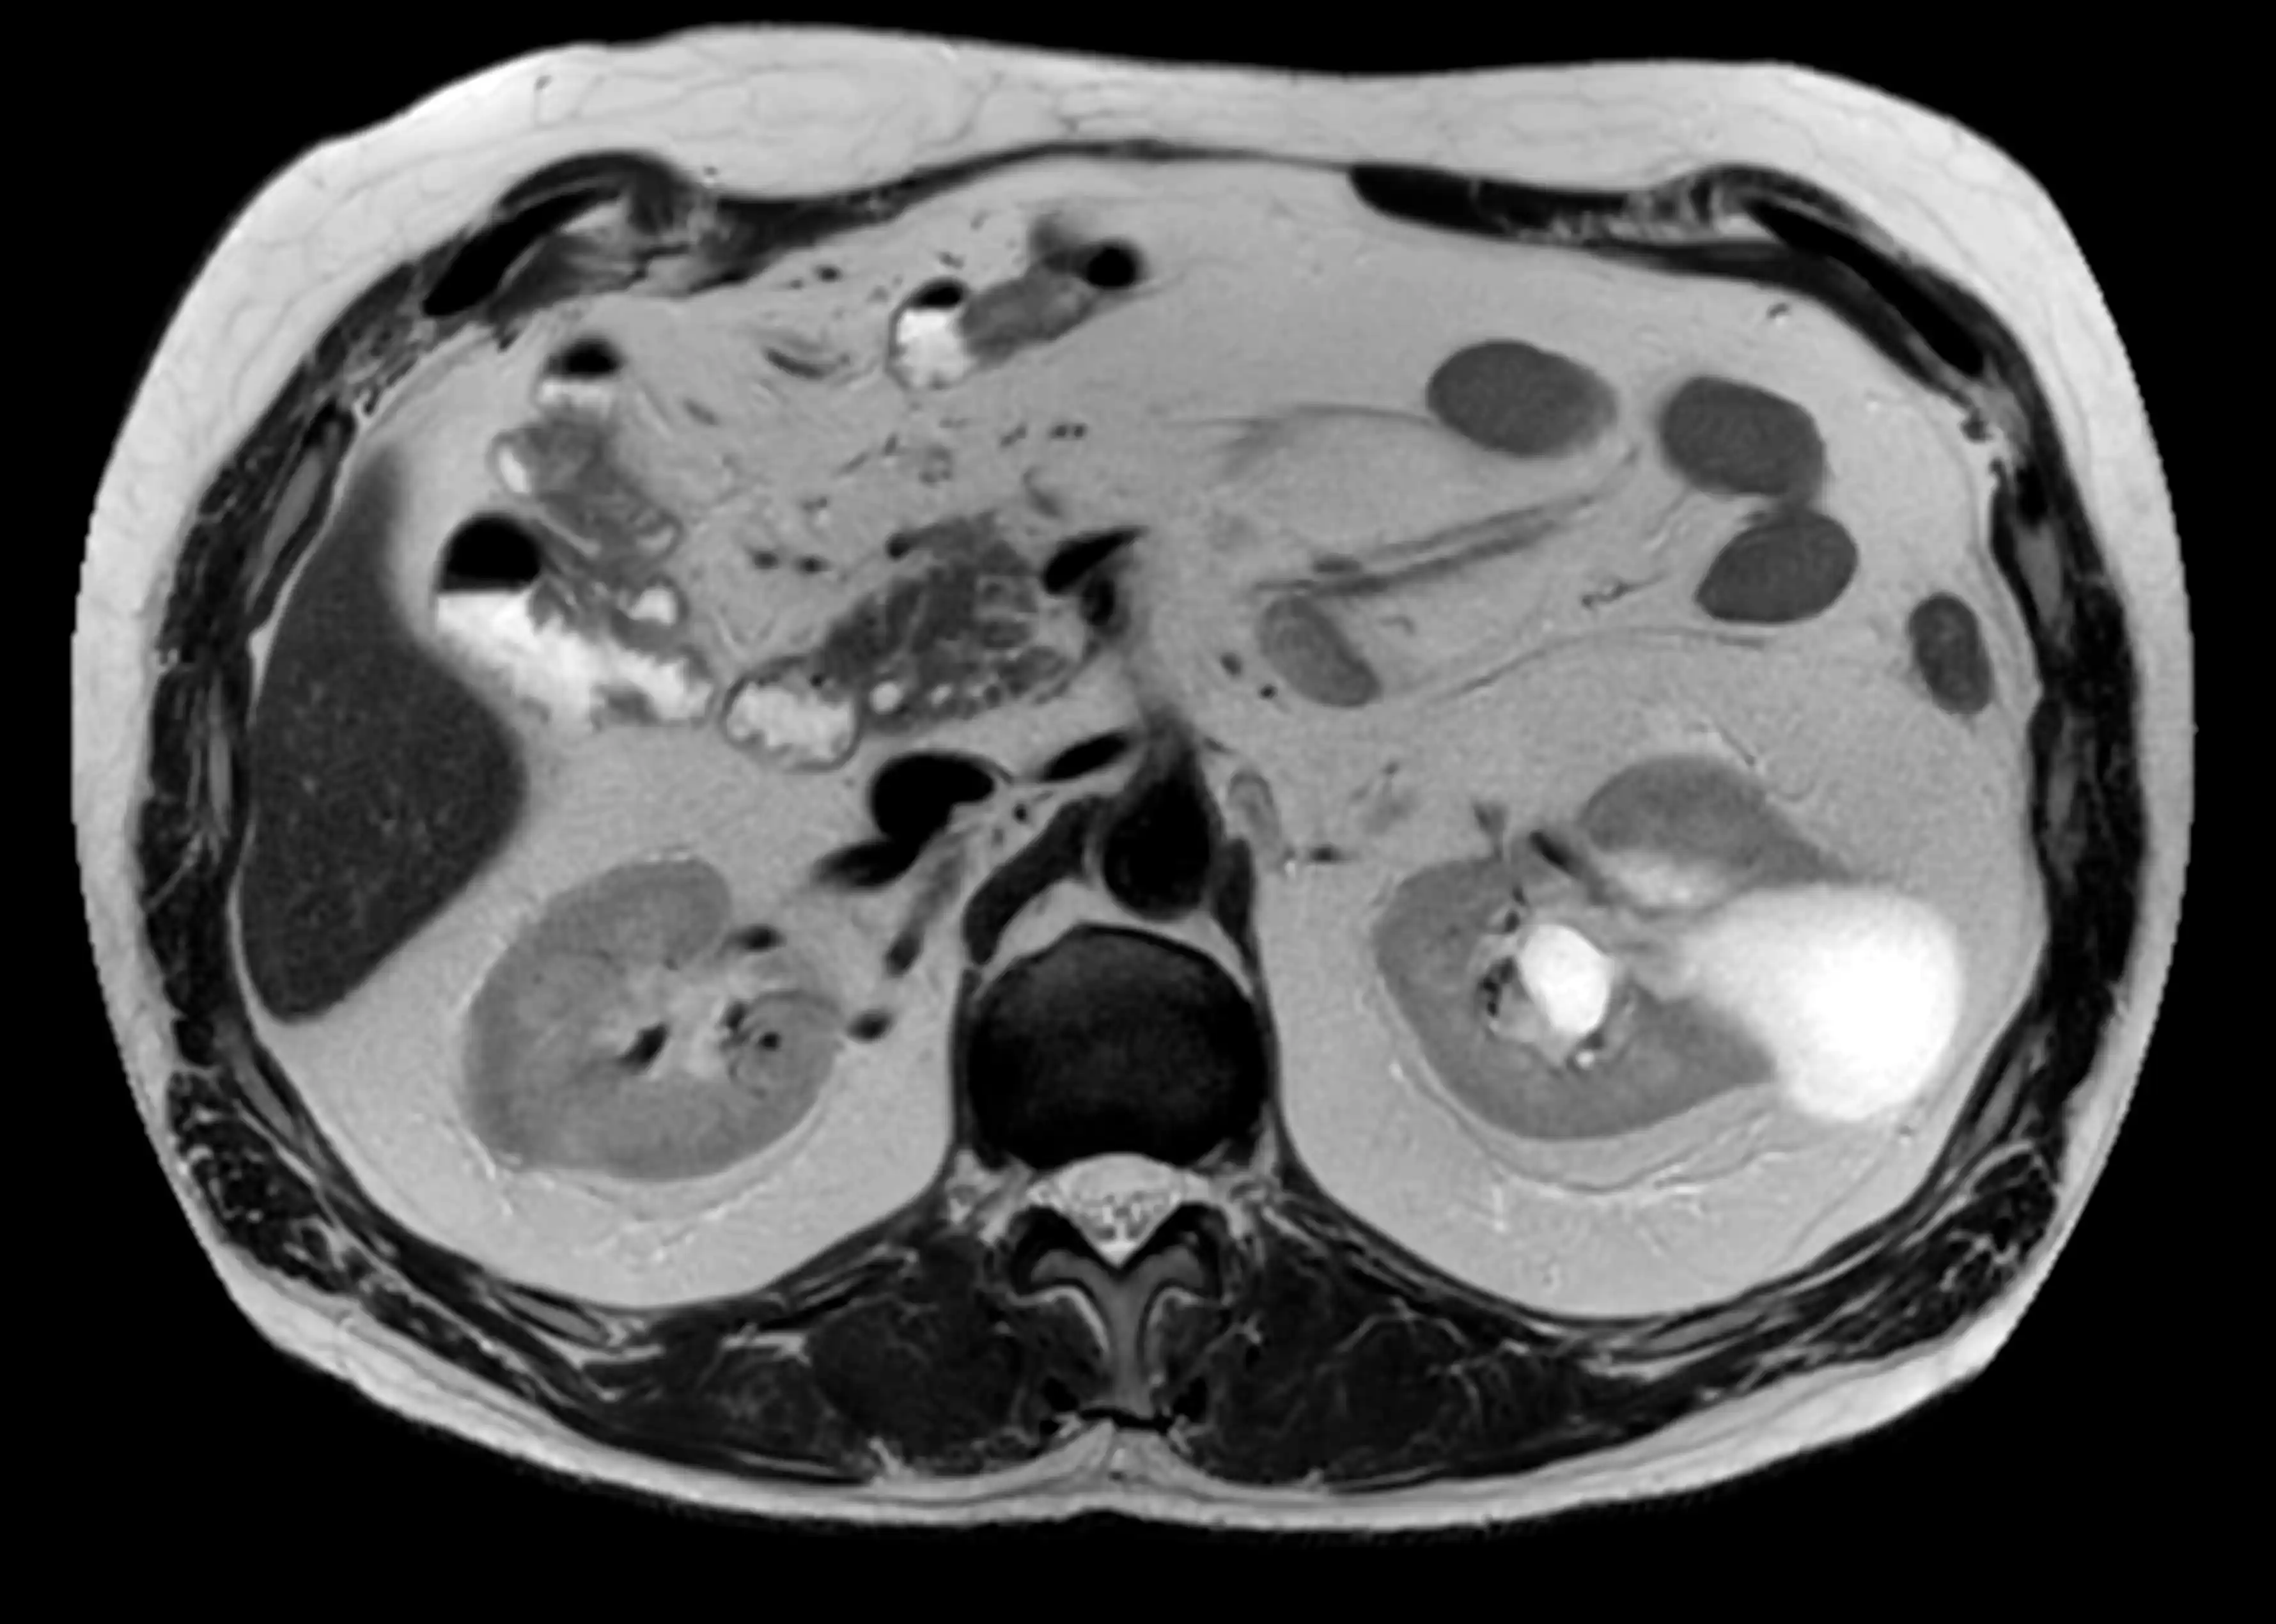

МРТ органів черевної порожнини — це сучасний, безпечний та високоточний метод обстеження, який дозволяє детально оцінити стан печінки, підшлункової залози, жовчного міхура, селезінки та інших внутрішніх органів.

Які органи досліджуються

МРТ дозволяє оцінити:

- печінку

- жовчний міхур та жовчні протоки

- підшлункову залозу

- селезінку

- нирки (за показами)

- лімфатичні вузли

- великі судини черевної порожнини